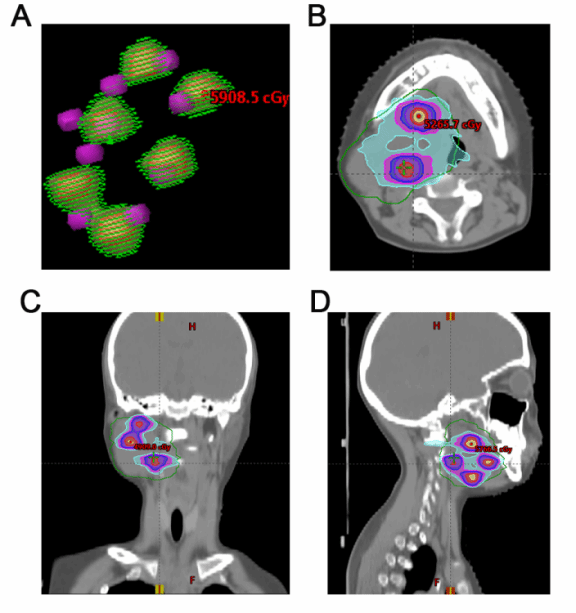

晶格放疗靶区示意图

该方案通过三维剂量调控,在肿瘤内部构建“高剂量顶点-低剂量周边”的梯度分布模式:高剂量区精准杀灭肿瘤核心,低剂量区保护周围正常组织并保留肿瘤血管,促进免疫细胞归巢和激活,形成“消融-免疫激活”协同效应。